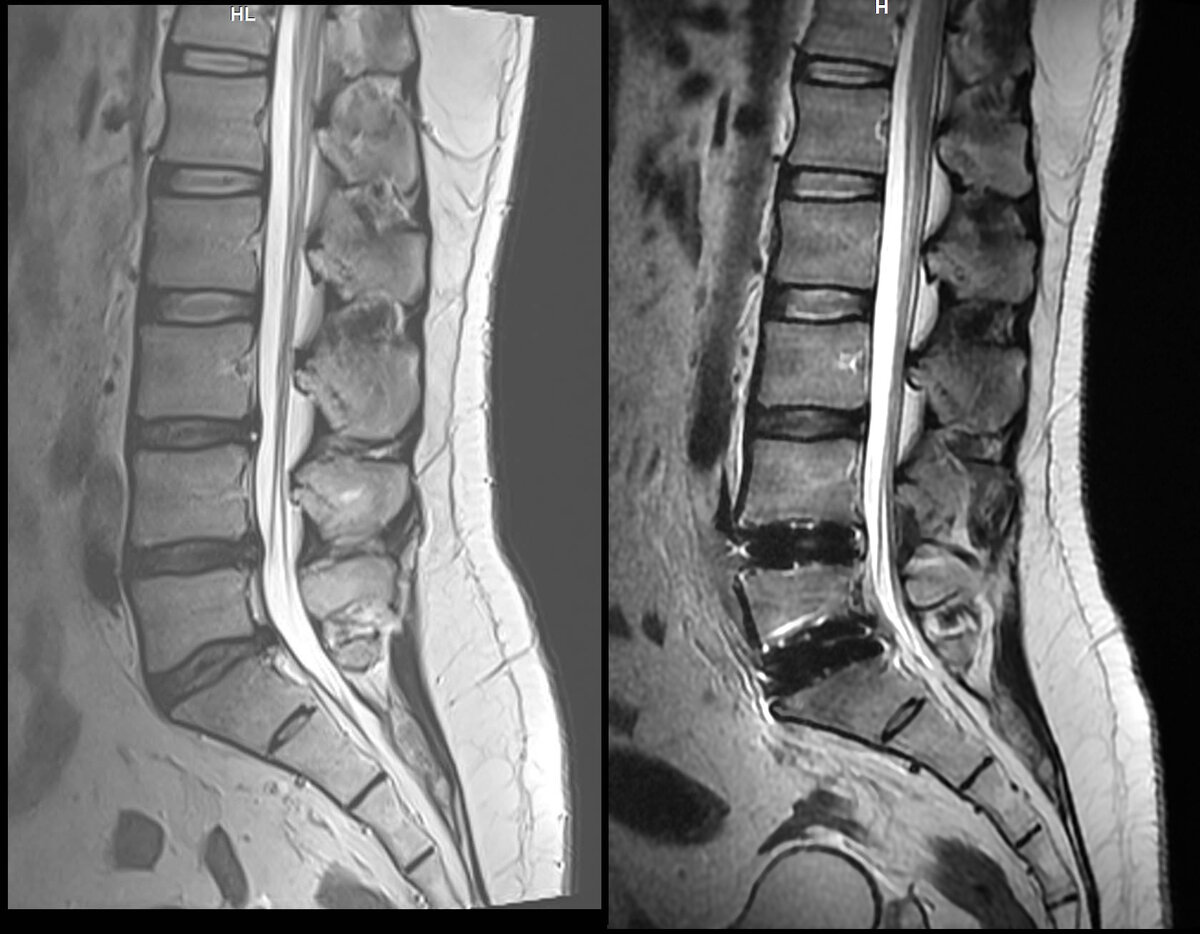

МРТ на 2ой день после операции. 2022г До и после. Более информативно будет через 3 месяца. Сейчас много отёков.